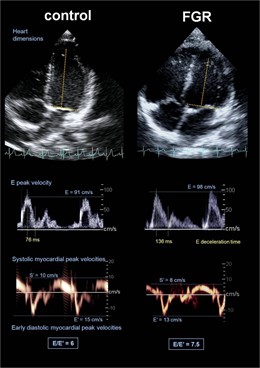

Radiografía. A La Izquierda, Corazón Bebé Normal Alargado. A La Derecha, Ensanch